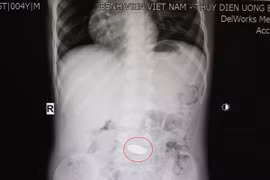

Các bác sĩ tại Bệnh viện Nhân dân Gia Định vừa thực hiện thành công ca nội soi, gắp dị vật vỏ thuốc cho người bệnh D.H.L, 18 tuổi, ngụ tại quận Bình Thạnh, TP HCM. Người bệnh cần thận trọng khi uống thuốc để tránh nhập viện cấp cứu.